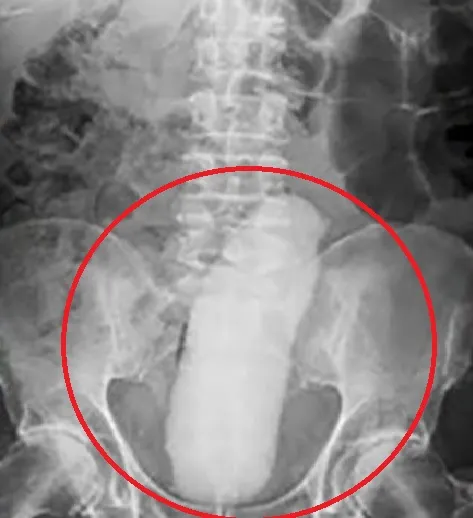

Um paciente do Hospital Vale do Guaporé, em Pontes e Lacerda (MT), fugiu da unidade médica horas após realizar uma cirurgia para retirar um objeto estranho alojado no reto. O caso aconteceu nesse sábado (21/6).

Conforme registro policial, realizado por um integrante da equipe médica, o rapaz foi até o hospital e após realizar a cirurgia, e saiu do local por volta das 16h30. A equipe apenas notou a ausência dele às 17h45 e viu que o paciente havia levado seus pertences com ele.